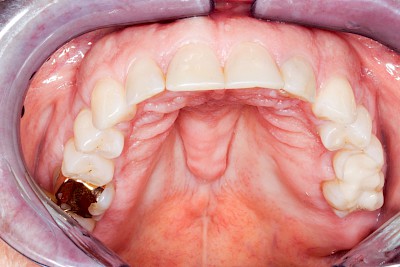

Gehen die Zähne verloren, baut häufig auch der Kieferknochen ab (Knochenschwund). Die Geschwindigkeit und das Ausmaß des Knochenschwundes ist von vielen Faktoren abhängig. Neben der genetischen Veranlagung spielen auch Überbelastungen in Folge, z. B. bei ständigem Knirschen oder Pressen, eine Rolle. Auch wenn Zahnprothesen Tag und Nacht getragen werden, kann die ständige Belastung der Schleimhäute und des Knochens den Knochenschwund beschleunigen.

Aber Achtung: Manche Menschen fühlen sich ohne Zahnprothesen unwohl. Zudem kann es passieren, dass Zahnprothesen (wenn noch eigene Zähne vorhanden sind) nicht mehr passen. Dies gilt vor allem dann, wenn diese Zahnprothesen nicht nur über Nacht, sondern für einen längeren Zeitraum nicht mehr getragen werden.

In seltenen Fällen schwindet nur der Knochen, aber nicht die bedeckenden Schleimhäute. In diesen Fällen spricht man von einem sogenannten "Schlotterkamm".

Heute werden in Deutschland Menschen mit Lippen-Kiefer-Gaumenspalten bereits ab Geburt von Experten verschiedener Fachrichtungen (Mund-Kiefer-Gesichtschirurgen, Kieferorthopäden, Logopäden) betreut, damit entsprechende Korrekturen schon frühzeitig erfolgen können. Gerade jedoch bei älteren Menschen ist dies nicht immer geschehen. Diese Menschen tragen häufig technisch aufwendige Zahnprothesen.